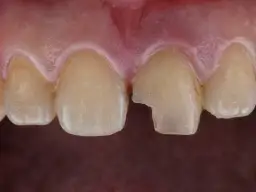

Kiedy brakuje miejsca: stłoczenia i uszkodzenia sąsiednich zębów

Współczesne szczęki często są mniejsze niż te, które były potrzebne naszym przodkom. W rezultacie, brakuje miejsca na prawidłowe wyrznięcie się wszystkich ósemek. Gdy ząb próbuje się wyrzynać w ciasnocie, może przyjąć nieprawidłowy kierunek wzrostu. Wówczas zaczyna naciskać na korzenie sąsiednich zębów, najczęściej siódemek. Ten nacisk może prowadzić do ich uszkodzenia, resorpcji korzeni, a także powodować stłoczenie pozostałych zębów, wpływając negatywnie na zgryz.